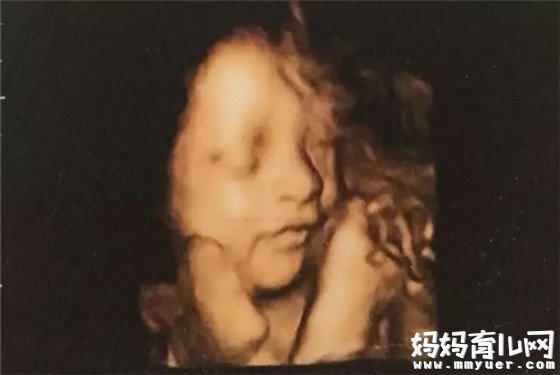

怀孕六个月就是从21-24周这个时间,可以从怀孕六个月的男胎儿图中发现,此时胎儿的皮肤依然是皱的,红红的,样子像个小老头。牙齿在这时也开始发育了,主要是恒牙的牙胚在发育。胎宝宝在子宫羊水中游泳并会用脚踢子宫,羊水因此而发生震荡。

怀孕六个月的胎儿身长30厘米,胎儿已长出头发,眉毛,睫毛,骨骼已经长得很结实,但还没有皮下脂肪,所以很精瘦。胎儿在充足的羊水中能够自由地移动身体的位置,甚至可以大头朝下"拿大顶"。皮肤表面开始附着胎脂。

骨骼更结实,头发更长,眉毛及睫毛开始长出。脸形也更清晰,已是十足人的模样。用听诊器可听出胎儿的声音。孕妇的肚子接近典型孕妇的体形,子宫底高18~21厘米。